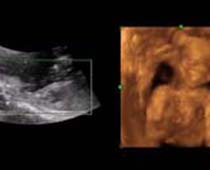

- The Clinical Advantages of 3D and 4D Ultrasound

- Definition and Features of Four Dimensional Ultrasound

- Uses of 4D Ultrasound scan

- 4D Ultrasound Scan Fetal Video Clips